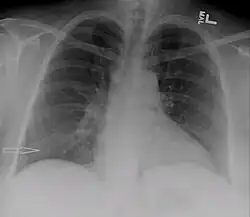

| Right sided pleural effusion caused by urinothorax | |

Urinothorax (pl. urinothoraces) is defined as urine in the fluid-filled cavity that surrounds the lungs.[1] It is usually caused by obstructive uropathy. It is mainly diagnosed by analyzing the pleural fluid. Treatment involves treating the underlying condition, which typically results in resolution of the urinothorax. It is an extremely rare cause of pleural effusion.[2]